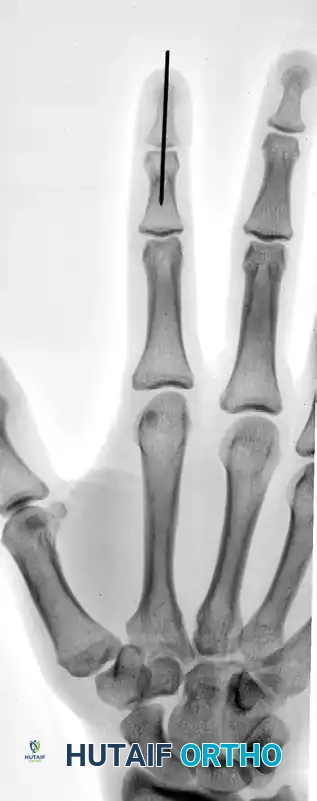

FIGURE 67-66 A: Type 4 bony mallet finger in a high-demand athlete, demonstrating a large dorsal fragment and volar subluxation of the distal phalanx.

FIGURE 67-66 B: Radiographic results of the pull-out wire and transarticular pin fixation of the distal interphalangeal joint, demonstrating anatomic restoration of the articular surface. Images taken just before pin removal at 4 weeks.

FIGURE 67-66 C: The pull-out wire is typically left in place until 6 weeks after surgery to ensure complete bony union before dynamic stress is applied.